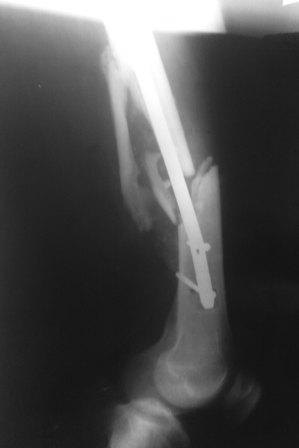

Пациент с политравмой. Выполнен помимо всего остеосинтез бедра стержнем. Поступил через месяц после операции с переломом фиксатора.У нас возникли разногласия по дальнейшей такике.Помогите пожалуйста советом! Пациент, 30 лет, после мотоциклетной аварии получил следующие повреждения: перелом бедра, перелом вертлужной впадины на противоположной стороне, перелом обоих предплечий, ЧМТ.Выполнен остеосинтез таза пластиной и остеосинтез бедра стержнем ChM. Во время операции стержень оптимальной длины оказался слишком "толстым" (420/11 мм) и пришлось выбрать более короткий гвоздь (400/10 мм). Через месяц возникла следующая картина: изгиб винтов и стержня, появилось смещение, имеется тугая подвижность в месте перелома.Предложено несколько выходов:- поменять фиксацию на более длинный гвоздь,- использовать ретроградную версию бедренного гвоздя,- поменять на накостный фиксатор (длинную LCP DF).В данном случае приобретать импланты придется за счет средств пациента, поэтому хотелось бы все тщательно взвесить.Уважаемые коллеги, помогите пожалуйста советом, как бы вы поступили в такой ситуации.

Большое спасибо за ответы. Прошу прощения, что сразу не показал боковую проекцию (прилагаю сейчас). Может быть с таким торцевым упором не производить динамичсекую фиксацию, а провести динамизацию позже.